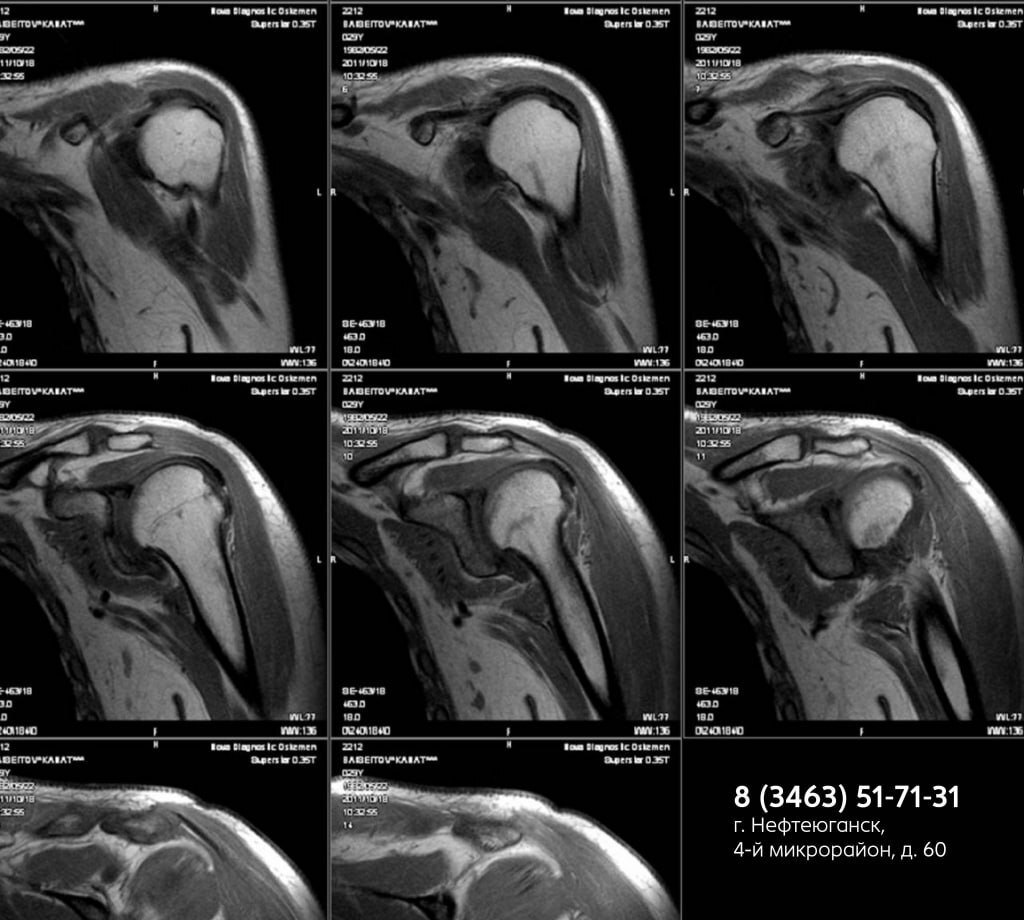

МР-сканирование послойно визуализирует ткани плеча с точностью до 1 мм, оценивая состояние:

• мягких тканей

• сосудов

• костей

• нервных корешков

Выявляем:

• воспаления, опухоли, трещины хрящей

• сдавливание сосудов, травмы, патологии суставов (артрит, тендинит, бурсит и др.)

• скрытые повреждения после ушибов, подвывихов

МР-исследование проводится при подозрении на патологии плеча: инфекционные, аутоиммунные, травматические, воспалительные, некротические, нейропатические и другие